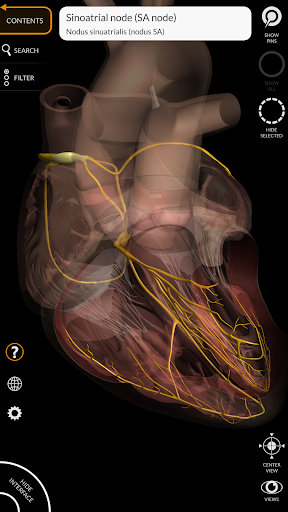

"Anatomy 3D Atlas" дозволяє легко та інтерактивно вивчати анатомію людини.

Завдяки простому та інтуїтивно зрозумілому інтерфейсу можна спостерігати кожну анатомічну структуру під будь-яким кутом.

Анатомічні 3D-моделі особливо деталізовані та мають текстури з роздільною здатністю до 4k.

АНАТОМІЧНІ 3D МОДЕЛІ

• Серцево-судинна система

• Нервова система